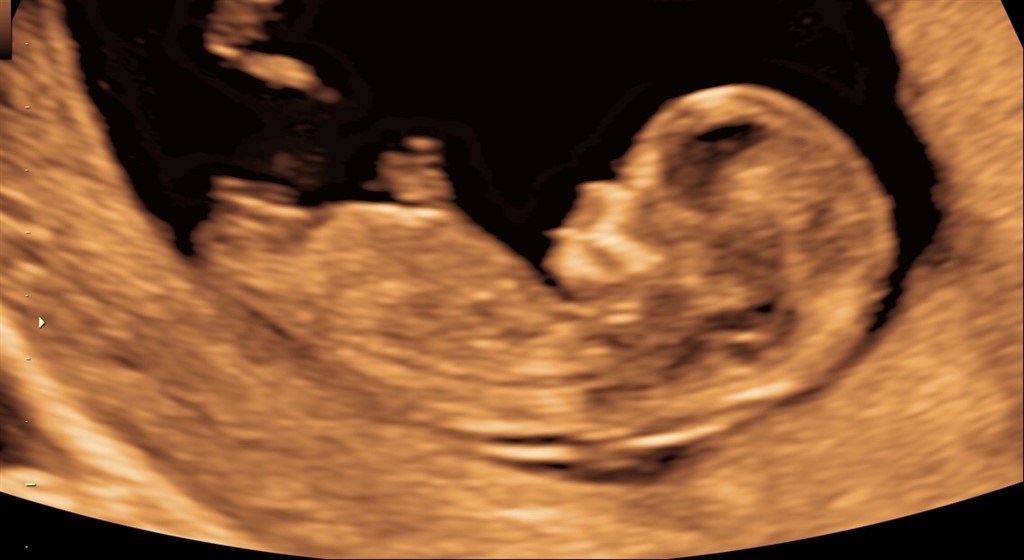

Nogen som har et gæt?

Vi skal ikke vide kønnet, men kunne være sjovt at høre hvad folk tror.. Scanningen er lavet 12+1

Vedhæftede fotos (klik for at se i fuld størrelse)